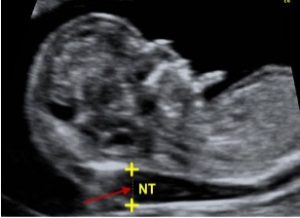

SIÊU ÂM ĐỘ MỜ DA GÁY: CÁC MẸ BẦU NÊN BIẾT CHO MỘT THAI KỲ MẠNH KHOẺ

Hiểu Về Siêu Âm Độ Mờ Da Gáy: Kiến Thức Quan Trọng Cho Thai Kỳ [...]